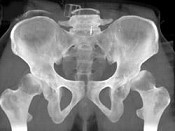

- 单项选择题男,23岁, 跛行,外展受限, 两下肢不等长,结合图像, 最可能的诊断是 ( )

A、髋关节中心脱位

B、髋关节后脱位

C、髋关节前脱位

D、先天性髋内翻

E、髋关节结核